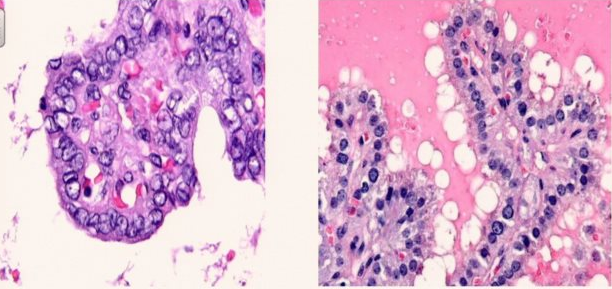

Which is Graves? Which is Papillary carcinoma? How do you know?

Papillary carcinoma is the one on the left - can tell because nuclei are empty-looking, enlarged, and have creases.

Which is Graves? Which is papillary carcinoma?

Graves is on the right, papillary carcinoma is on the left. Similar architecture but the nuclear cytology is very different!

What is this? What are some important features?

Papillary carcinoma. Papillary cores, blood vessel, and empty-looking nuclei.

Arrow?

Nuclear inclusion (seen in papillary carcinoma)

Nuclear groove seen in papillary carcinoma